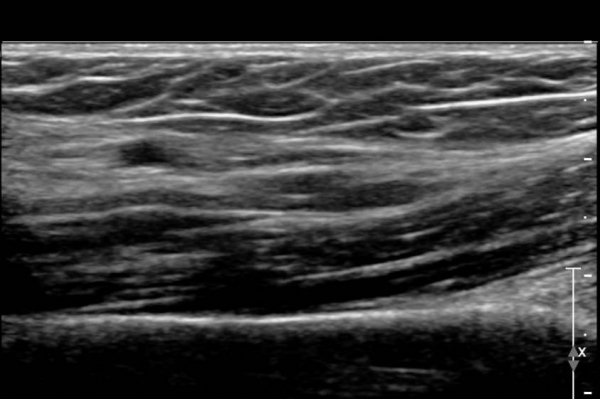

¾Æ·§ÆÈ¿¡¼­ Àü°ñ°£ ½Å°æºÎÀ§ Ⱦ´Ü¸é°Ë»ç»ó ¾öÁö ±¼±ÙÀÇ °í¿¡ÄÚ º¯¼ºÀÌ °üÂûµÇ°í  Àü°ñ°£µ¿¸Æ

ÁÖÀ§¿¡¼­ Á¾±« µî Ưº°ÇÑ ÀÌ»ó ¼Ò°ßÀÌ °üÂûµÇÁö ¾Ê´Â´Ù(»çÁø 1).